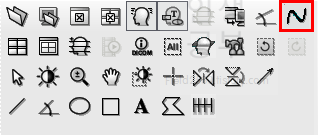

목의 정렬을 알아보기 위해서 목뼈의 선들을 연결해서 그어보는 방법에 대해서 알아보겠습니다. 도구 상자에서 빨간색네모상자 안에 있는 물결무늬 모양의 버튼을 눌러줍니다.